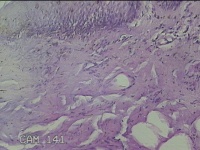

肛周外痔

1.出血性内痔 2.混合痔 3.肛乳头肥大

一般病史

间断便血3年余。

标本名称

大体所见

灰白暗红色包块0.7x0.3x0.2cm一个,表面糜烂。

像痔。

有可能是外痔。猜的。